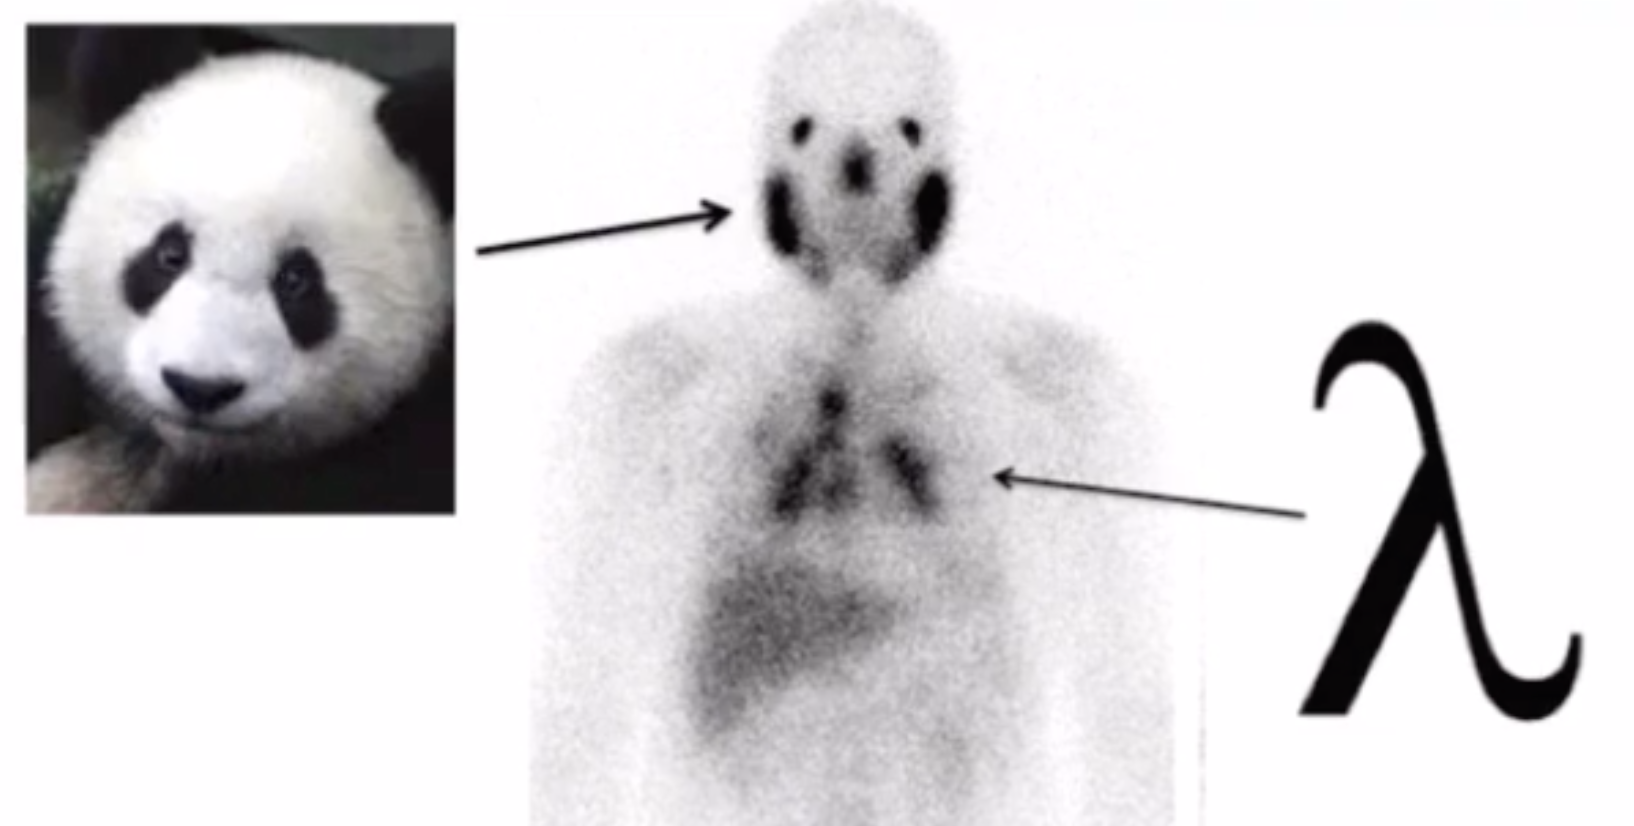

Sarcoidosis

• Lambda sign

• Hilar lymphadenopathy looks like greek letter lambda

• Panda sign

• Seen on Gallium-67-citrate studies

• Uptake in parotid and lacrimal glands (abnormal) and nasopharyngeal tissue (normal) makes it look like face of a panda

• Lymphoma and Sjogran also in differential